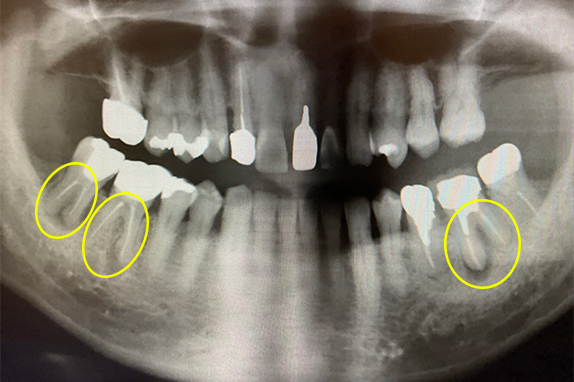

右の奥歯が痛くて噛めないという主訴で来院。7番をマイクロエンドで完全し6番にインプラントを埋入したケースです。

CASE 02 マイクロエンド(精密根管治療)+歯周基本治療

右も左も痛くて噛めないという主訴で来院。マイクロエンドをし歯周基本治療で改善したケースです。